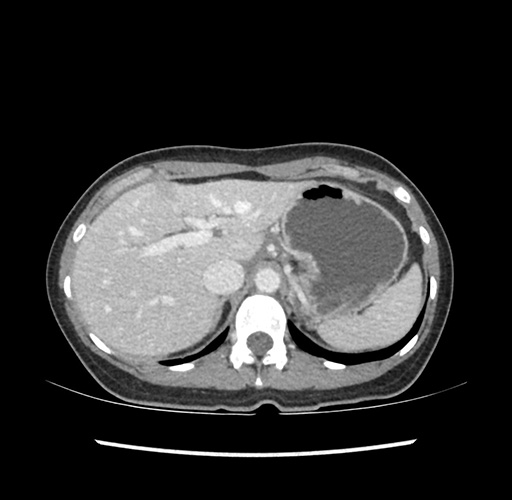

Imaging Analysis

Look through the patient's CT scan to identify any areas of concern for the necessary procedure.

Based on your CT findings, which issue(s) would give reason for "planned slowing down moment(s)" in this case?

Considering a standard left lateral sectionectomy procedure, what step(s) of the operation would you do differently in this case ?